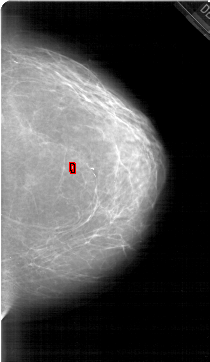

A_1452_1.RIGHT_CC

RIGHT_CC LINES 6511 PIXELS_PER_LINE 3766 BITS_PER_PIXEL 12 RESOLUTION 43.5 OVERLAY

FILE: A_1452_1.RIGHT_MLO.OVERLAY

TOTAL_ABNORMALITIES 1

ABNORMALITY 1

LESION_TYPE CALCIFICATION TYPE PLEOMORPHIC DISTRIBUTION CLUSTERED

ASSESSMENT 4

SUBTLETY 4

PATHOLOGY BENIGN

TOTAL_OUTLINES 1